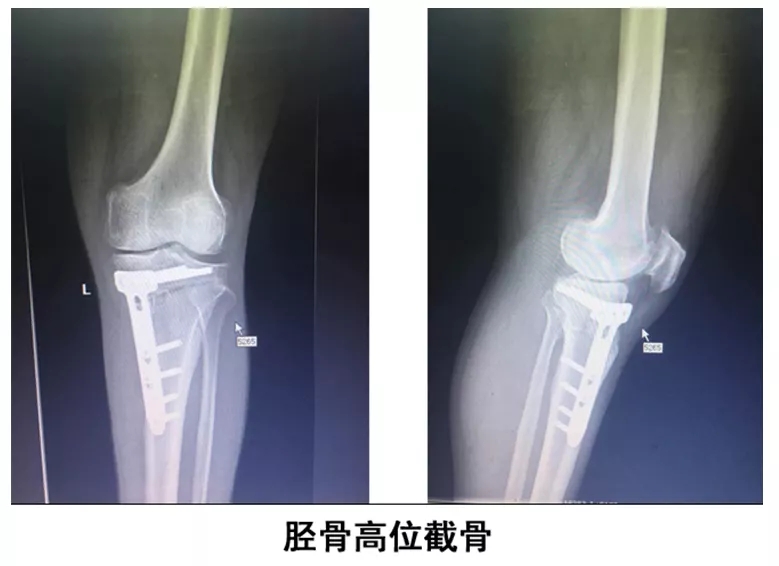

胫骨高位截骨术:

胫骨高位截骨术,是通过胫骨近端截骨,改变力线,将力线从磨损的内侧间室转移至相对正常的外侧间室,延缓内侧间室的破坏,控制骨性关节炎的进展,保留膝关节的交叉韧带功能,解除膝关节疼痛,延长膝关节的使用寿命,使患者可以恢复较高水平运动甚至竞技运动,推迟或者避免膝关节置换术。60岁以下膝关节外胫骨畸形患者,经此手术不需置换,通过矫正下肢负重力线解除患者膝关节疼痛,可达到日常正常的运动水平。